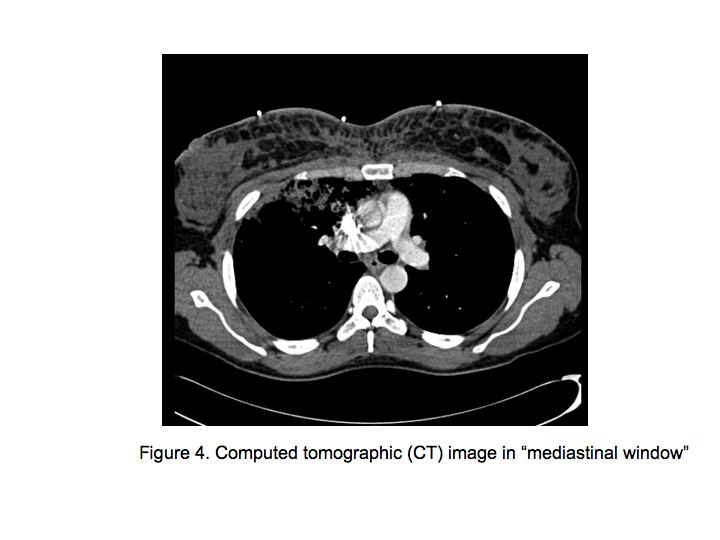

Upon further questioning triggered by the observed skin needle marks, the patient attributed them to hormonal injections and multiple subcutaneous inoculations with a substance which on the vial had no name, but the following chemical structure: Si(CH3)3-[C(CH3)2-Si-O]n-Si(CH3)3 .

The patient was admitted to the medical floor and was started empirically on antibiotics. Cultures were obtained and an HIV test was done. Bronchoscopy was planned the next day which revealed diffuse erythema and hemorrhage in both the bronchial trees as shown in Fig. 5.